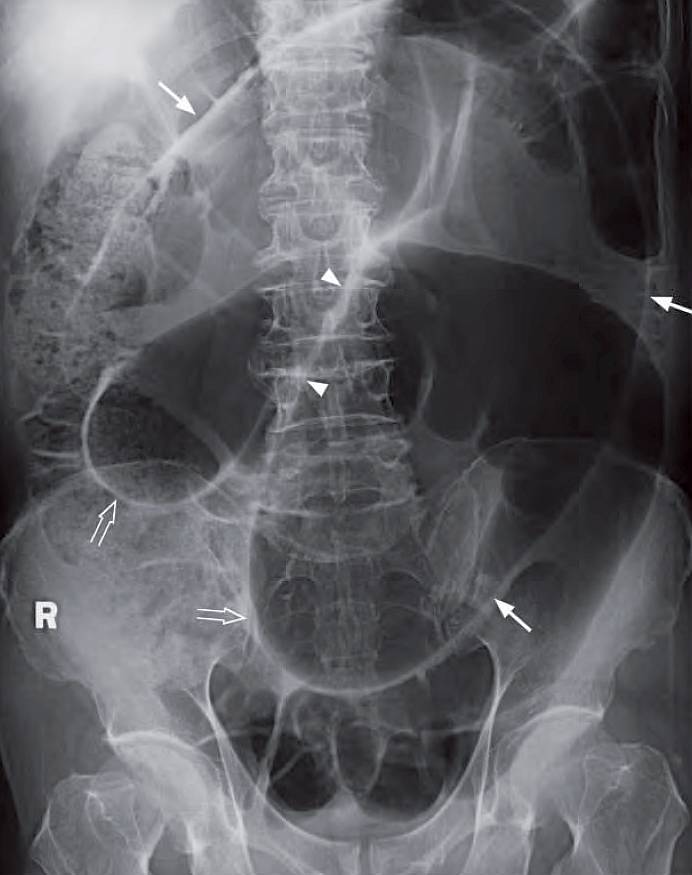

An 86-year-old woman complained of sudden onset severe colicky lower abdominal pain for 4 hours. This was associated with vomiting and constipation.

Physical examination showed that she was in agony with stable BP and pulse. The abdomen was distended, with marked local tenderness and guarding over the central lower abdomen. There was no physical sign of inguinal or femoral hernia. Laboratory investigations showed normal white cell count.

What’s the diagnosis and what radiological abnormalities can you detect ?